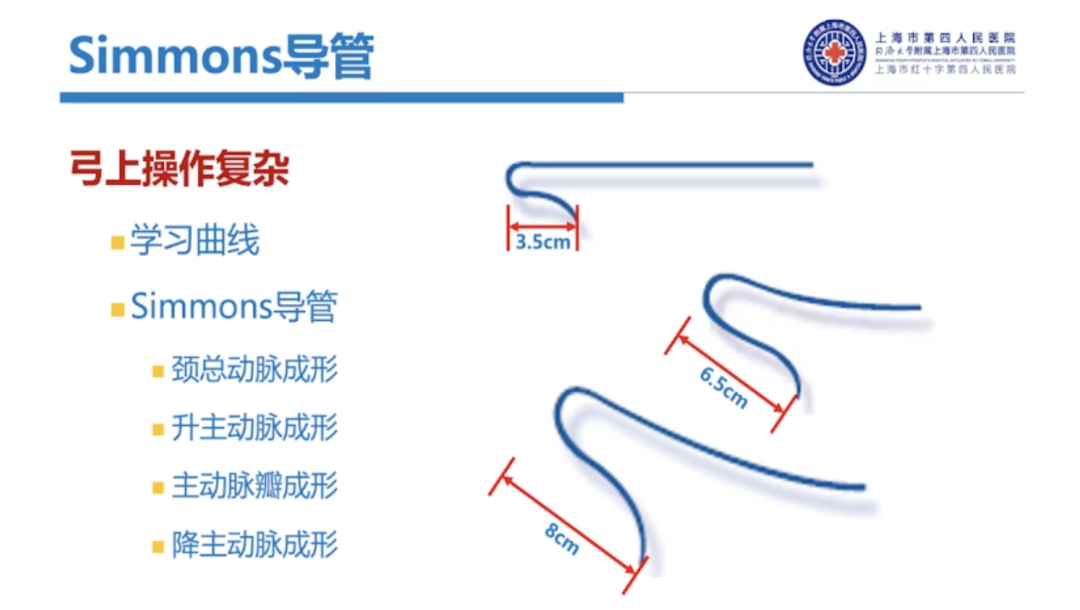

不同Sim导管尺寸对弓上超选也是有影响的,通常在右侧颈总动脉成型、升主动脉成型时更常用Sim I,Sim I头端较短,非常容易通过主动脉弓进入降主动脉。

主动脉瓣成型一般使用较少,但是如果弓型比较特殊,我们使用Sim I导管完成主动脉瓣成型还是非常有效的,对于降主动脉成型以及左侧经桡成形,我们一般会选择Sim II。